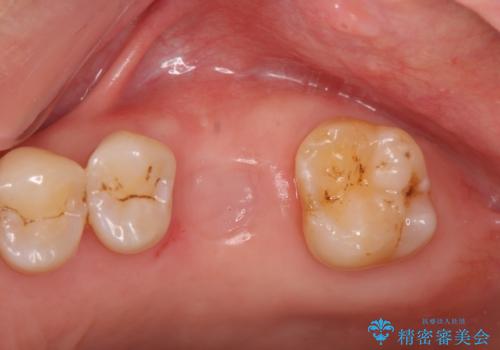

- 歯が割れてしまい、抜歯後のインプラント治療を希望され相談来院されました。

歯の喪失後に失われた咬合機能を回復するため、ブリッジ・入れ歯・インプラントの治療提案を行いました。

それぞれの長短所を検討し、隣接する歯を削らずにすみ、咬合機能をもっともしっかり回復できるインプラント治療を希望されました。